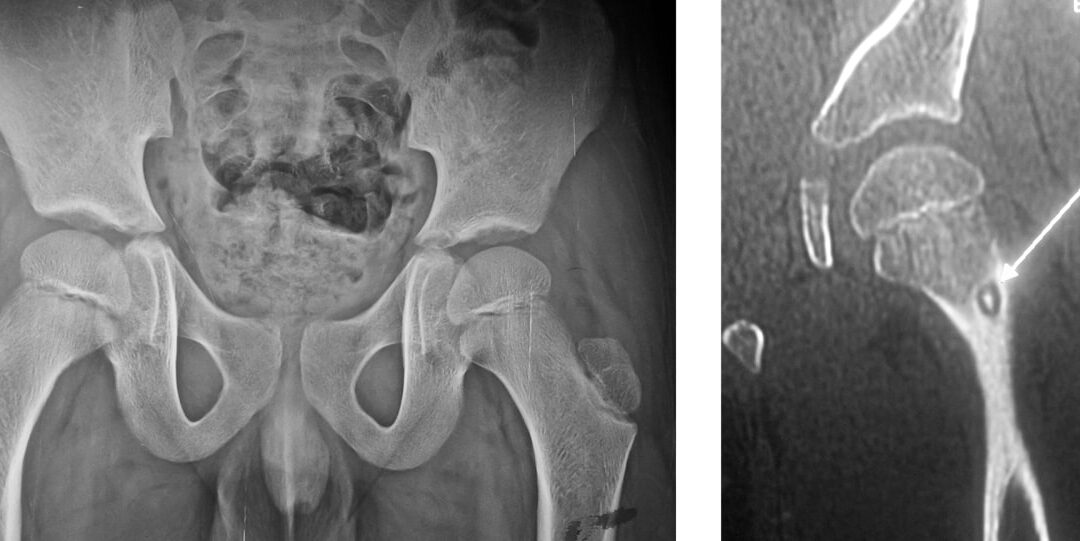

What is Developmental Dysplasia of Hip? The hip joint is a ball and socket joint in which the femoral head (ball) articulates with the acetabulum (socket) (Figure 1). Figure 1: The hip joint is a ball-and-socket joint. Developmental Dysplasia of Hip...